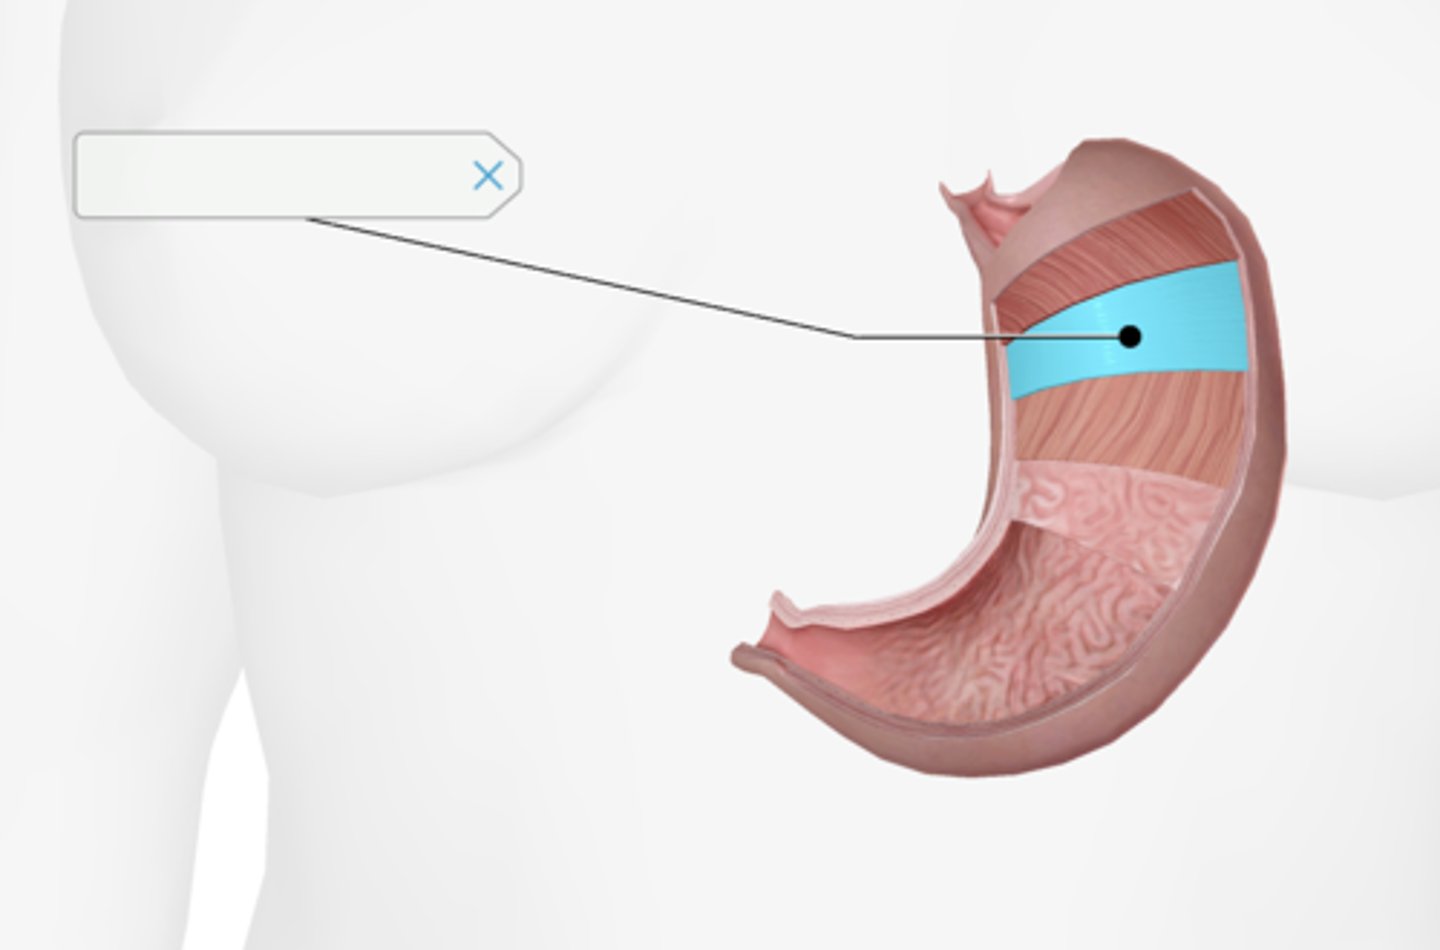

Cardiac sphincter

Longitudinal muscle layer of the stomach

Oblique muscle layer of the stomach

Circular muscle layer of the stomach